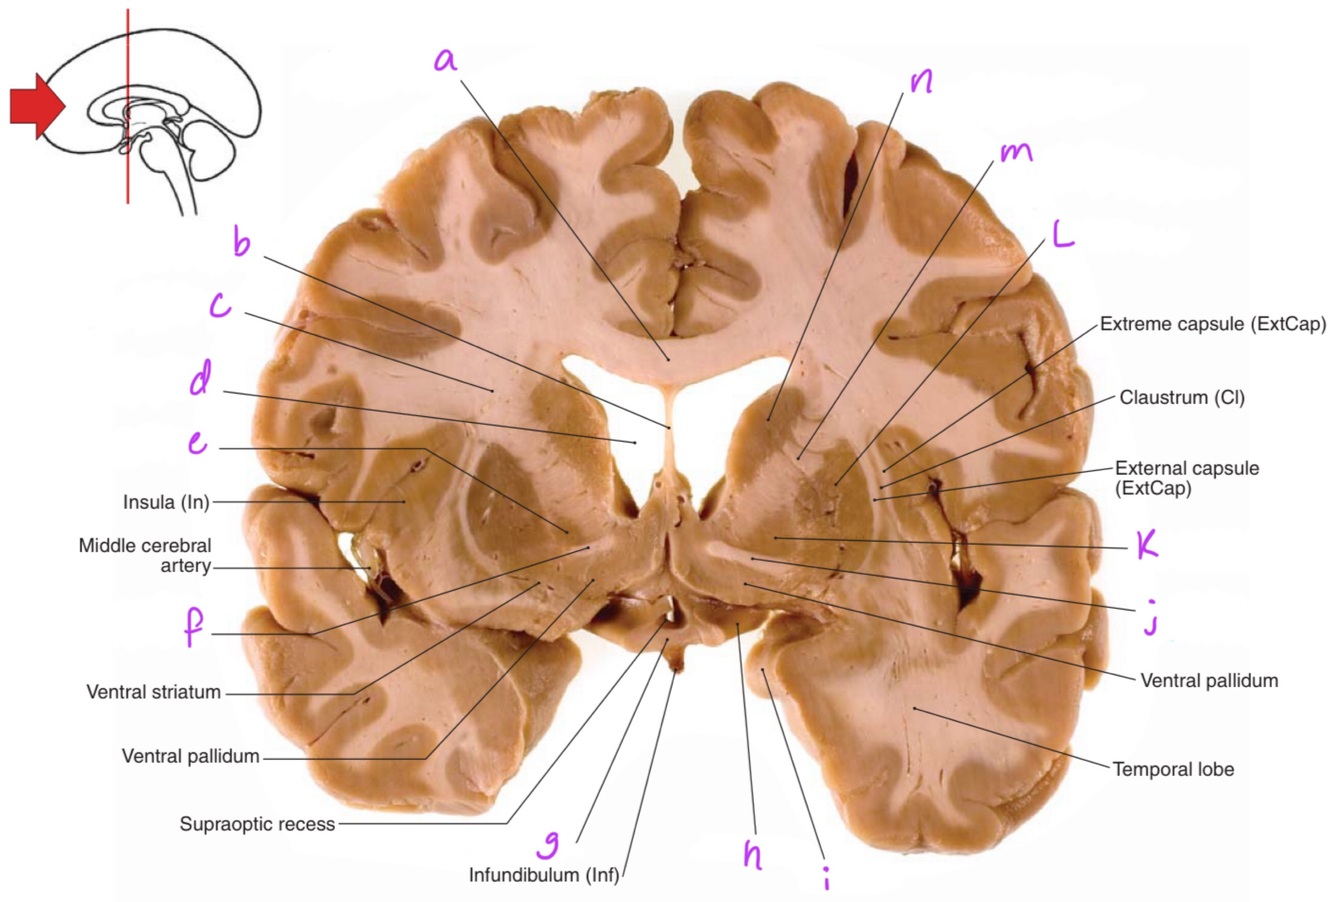

a

body of corpus callosum

b

Anterior horn of lateral ventricle

c

Septum pellucidum

f

g

Putamen

1

2

4

Perfectly

Q

How well did you know this?

Not at all

Corona radiata

e

Globus pallidus

Anterior commissure

Optic chiasm

Optic tract

Uncus

Anterior limb of internal capsule

n

Head of caudate nucleus